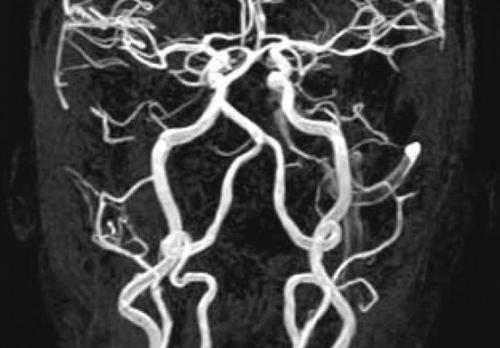

Исследование кровеносной системы применяют в хирургии, онкологии, неврологии и других направлениях медицины. МРТ заданной области с МР-ангиографией позволяет оценить функциональность, наполненность, просвет, состояние стенок вен и артерий.

По результатам сканирования определяют характер кровоснабжения рассматриваемой зоны, выявляют очаги ишемии, некроза. При травмах томограммы визуализируют гематомы, нарушение целостности сосудистой стенки.

Анализ результатов магнитно-резонансной ангиографии выполняет врач МРТ. В протоколе исследования указывают:

- диаметр, проходимость сосудистого русла;

- состояние стенок, наполненность сосуда;

- наличие в просвете посторонних частиц (эмболов);

- локализацию пораженного участка;

- состояние окружающих тканей;

- функциональность вен и артерий;

- степень нарушения кровообращения в тканях;

- причины геморрагических и ишемических явлений.

МРТ исследование в режиме ангиографии назначают перед хирургическим вмешательством. На основании результатов сканирования определяют локализацию и протяженность пораженного участка, уточняют характер патологии и объем предстоящей операции.

В период реабилитации с помощью МР-ангиографии контролируют процессы восстановления, МРТ помогает своевременно диагностировать развитие осложнений.

Сканирование позволяет отслеживать течение хронических заболеваний. В этом случае МРТ ангиографию сосудов назначают с частотой 2 раза в год. Раннее выявление рецидивов способствует своевременной коррекции лечения и помогает добиться стойкой ремиссии.